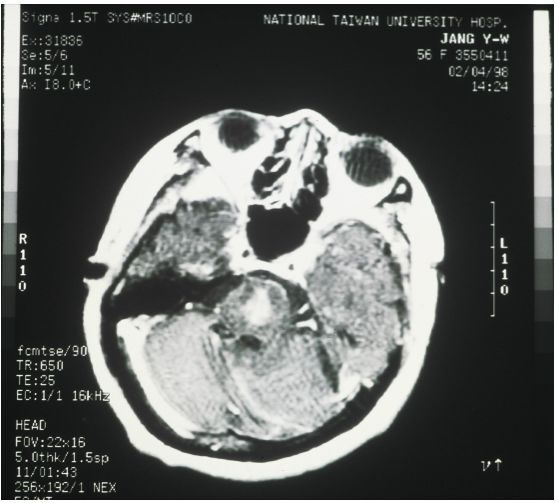

7. 承上題經過治療後三天,病人出現意識更加模糊、conjugate gaze出現障礙、四肢輕癱(quadriparesis),電腦斷層攝影如圖73 。下列何者敘述正確? (A) 如果在矯正低鈉血症時,同時給予10%mannitol可以預防這種病變。 (B) 通常這樣的病變是低鈉血症矯正太慢所致。 (C) 以下的治療可以減少或避免發生病變:以3%NaCl靜脈灌注,速度是0.05 mL/Kg/min以下。 (D) 矯正時必須每小時測定血清鈉,一直到血清鈉達到135 mmol/L為止。 (E) 或者血清鈉增加15 mmol/L為止。